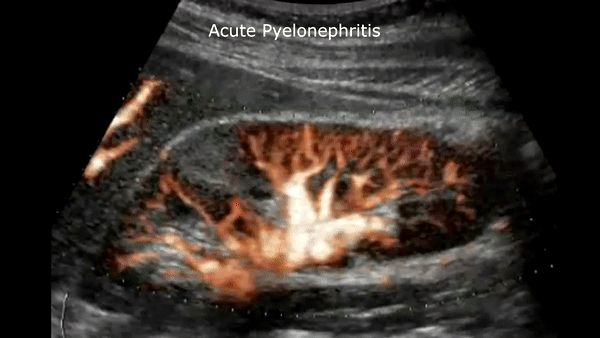

Acute pyelonephritis

Bacterial inflammatory disease of the kidney is commonly cause Eschericia coli. Most infections begin as UTI that ascends to the upper genitourinary system. the infection spreads from the renal pyramids into the renal cortex. The infection may be focal or diffuse. This condition usually presents with chills, fever, flank pain and laboratory findings of urinary infection.

Ultrasound may show an enlarged kidney with edema and increased echogenicity. You may also see a focal triangular area of altered echogenicity that displays reduced perfusion with color Doppler and power Doppler. If left untreated or inadequately treated that area can turn into an abscess.